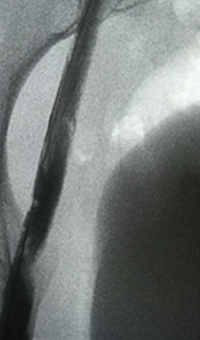

Case CLI with right foot ulcer thrombectomy: Posterior and anterior tibial

Case CLI with Right Foot Ulcer Thrombectomy pre-procedure arteriogram.

Arteriogram of posterior and anterior tibial post-CDT

PT and AT remained occluded following overnight CDT infusion of lytic

Case CLI with Right Foot Ulcer Thrombectomy post-AngioJet Solent Dista.

Post-AngioJet™ Solent™ Dista thrombectomy with PowerPulse™ delivery

AngioJet Solent Dista Catheter used in Power Pulse mode in both AT and PT. 30 min dwell in  AT and 45 min dwell in PT. Followed by Solent Dista Catheter used in thrombectomy mode

Case CLI with Right Foot Ulcer Thrombectomy post-procedure arteriogram.

Post-procedure arteriogram

Image following ballooning of small focal lesion in PT